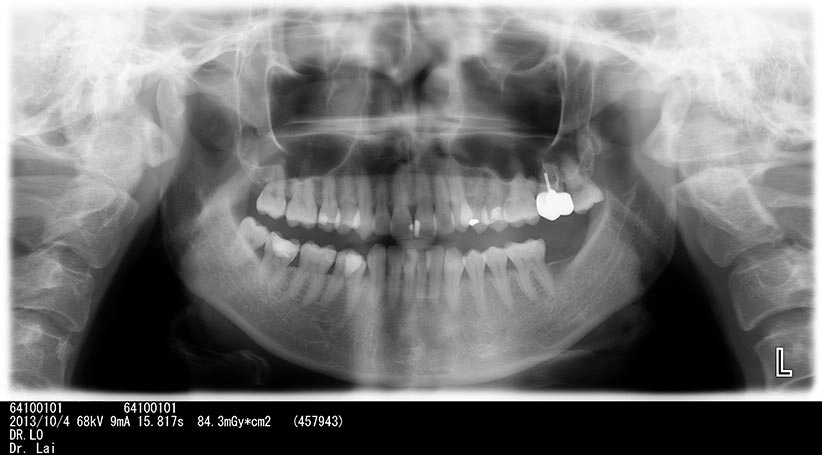

不拔智齒後果

左右下牙兩顆智齒不聽醫師建議拔除,5年後,智齒前面大牙也因智齒而蛀牙,最後拔除4顆牙

左下智齒不聽醫師建議拔除,5年後,智齒前面大牙也因智齒而蛀牙,最後拔除2顆大牙